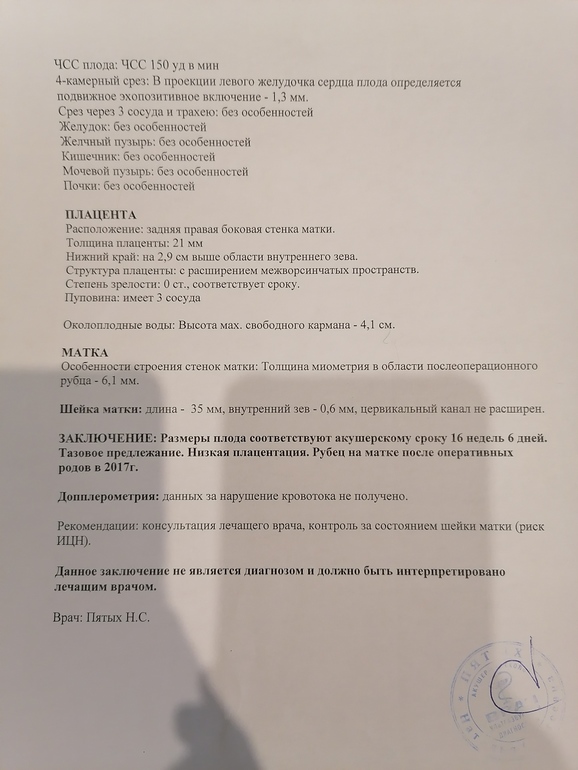

Добрый день, мои хорошие🤗. Нам сегодня 16 недель, сыночек растёт ттттт хорошо. Вчера пнул меня в руку 4 раза, это уже не внутри шевелюшки, а чувствуютс я через живот. Это нереальные ощущения🥰🙏🙏🙏👶.

Добрый день, мои хорошие🤗. Нам сегодня 16 недель, сыночек растёт ттттт хорошо. Вчера пнул меня в руку 4 раза, это уже не внутри шевелюшки, а чувствуютс я через живот. Это нереальные ощущения🥰🙏🙏🙏👶.

Такая картинка была на 2 скрининге.

Ну сегодня врач сказала, скорее всего лежал не удачно и так ответило на узи. Сегодня все отлично ттттт.

В любом случае на таком сроке до 6 мм норма. Многие не знают, паникуют

Ну вот видимо так и есть все от незнания. Поэтому я и поехала на экспертное узи

Слушайте, как здорово! Какие приятные новости😊подскажите пожалуйста, а где принимает Пятых? И можно её координаты в личку для записи на узи? А то я сегодня что-то расстроилась, что мне по скринингу написали высокий риск маловесного ребенка, никогда такого не было, стала переживать((( врач в жк толком ничего не сказала(((

Обязательно сходите, шикарная врач, прям вот от души советую. И фото штук 20 дала. Она принимает в клинике " Я здорова" проспект Андропова 42 корп. 1. Прям звоните и записываетесь. Я вчера позвонила и на сегодня запись была. Клиника хорошая и аппарат узи шикарный.

Ооо, УЗИ у Н.С. )) Она хороший узист. Сама к ней хожу, к Тё сложно попасть.

Спасибо. Да к нему совсем ничего не было и это в двух клиниках, а к ней сразу записалась. И мне она очень понравилась

Я ходила к ней в 15.6, у нас с вами параметры мальчуковые похожи, тоже опережаем. Носик у моего тоже скромный, 3,8 мм.

Поздравляю с хорошим узи)) напугают же какими то отеками складки.....(

Да, прекрасный специалист с огромной любовью к работе, карапузикам и их мамам)

Да реально испугались и вещи НИПТ хороший и скрининг, а тут на те. Я теперь тоже её фанат🙈🥰😂😂

Я тоже первый у него делала, но я от Пятых в восторге, она супер

Да, она отличная врач! Стараюсь тоже все узи делать только у нее. Все покажет, расскажет, успокоит. На что надо, обратит внимание. У меня полип цк- видит только она, у остальных- вроде что-то есть...не могу точно сказать! Если что-то увидет- будет следить за этим на последующих приемах.

Да видно, что грамотный врач и как человек шикарная.